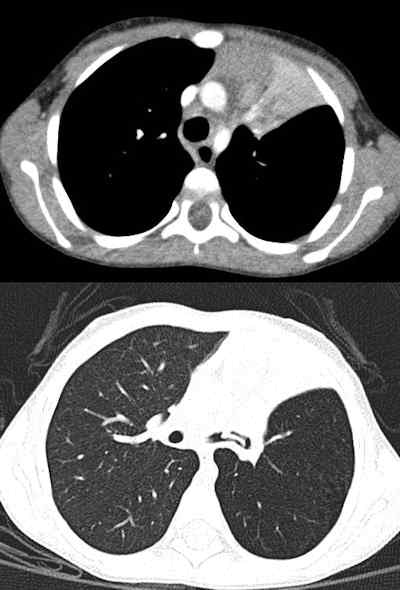

![Chest CT of 8-day-old girl with respiratory distress (80 kV, 51 average effective mAs, CTDIvol = 2.3 mGy, DLP [dose length product] = 33 mGy cm, E[effective dose] = 1.1 mSv. CT was performed to exclude congenital lung abnormalities because of family history and small volume lungs. Image shows ground glass opacity and septal lines consistent with respiratory distress syndrome. In all four figures, CTDIvol and DLP are expressed in terms of the 16 cm CT dosimetry phantom; these should be divided by approximately two to be expressed in terms of the 32 cm CT dosimetry phantom. Effective dose was calculated from DLP using conversion coefficients specific to this scanner and using the International Commission on Radiological Protection Publication 103 definition of effective dose. All images courtesy of Zoe Brady, PhD.](https://img.auntminnieeurope.com/files/base/smg/all/image/2012/08/ame.2012_08_15_08_57_30_715_2012_08_15_pediatrict_CT_pic1.png?auto=format%2Ccompress&fit=max&q=70&w=400)

The researchers compared average dose values at the Royal Children's Hospital (RCH) in Melbourne with international DRLs for common pediatric CT examinations. They found the use of 80 kV for both chest and abdomen/pelvis imaging in children younger than 5 years old leads to a significant dose saving, but conceded there is potential for dose optimization by reducing scan lengths for body examinations for children older than 5 years old. The plan now is to review these protocols to determine whether there is appropriate justification for the extended scan lengths.

Furthermore, the reference mAs values for chest imaging must be justified, particularly relative to the abdomen/pelvis examination values for the same age groups, according to Brady. Because of the inherent contrast in the chest and lack of attenuating tissue, it was expected that these values might be lower for chest examinations than for abdomen/pelvis examinations, but in fact in the older age group they were found to be higher.

The authors carried out a retrospective audit of patient records for pediatric CT brain, chest, and abdomen/pelvis exams. Demographic information, exam parameters, and dose indicators (volumetric CT dose index [CTDIvol] and dose-length product [DLP]) were collected for 220 patients: 100 for CT brain exams and 60 for each of the CT chest and abdomen/pelvis exams. Local DRLs (LDRLs) were derived from mean survey values and the effective dose was estimated from DLP values. The normalized CTDIvol values, mAs values, and scan length were assessed to better identify parameters that could be optimized.

The LDRLs across all age categories were 18-45 mGy (CTDIvol) and 250-700 mGy cm (DLP) for brain examinations; 3-23 mGy (CTDIvol) and 100-800 mGy cm (DLP) for chest examinations; and 4-15 mGy (CTDIvol) and 150-750 mGy cm (DLP) for abdomen/pelvis examinations. Effective dose estimates were 1.0-1.6 mSv, 1.8-13.0 mSv and 2.5-10.0 mSv for brain, chest, and abdomen/pelvis examinations, respectively. The RCH mean CTDIvol and DLP values were similar to or lower than international DRLs.